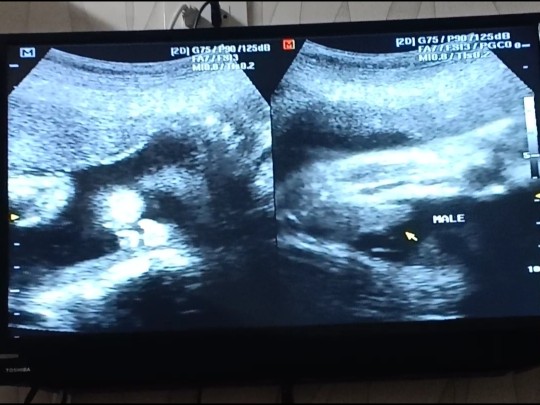

แม่ที่ได้ลูกชาย เห็นเพศตอนกี่เดือนคะ เราท้อง 3 เดือนครึ่งเมื่อกี้มีคนถามว่ารู้เพศหรือยัง เราบอกว่ายังไม่รู้เลย เขาบอกสามเดือนถ้าไม่เห็นเเสดงว่าเป็นผู้หญิง อันนี้จริงมั้ยคะ แฟนอยากได้ผู้ชาย แต่ถ้าได้ผู้หญิงก็ดีค่ะเราชอบเด็กผู้หญิง

บ้านนี้เห็นตอน 16 วีคพอดีค่ะ ผู้ชายเห็นง่ายกว่าผู้หญิง

บ้านนี้ตอน5เดือนคะ โชว์คุณหมอให้เห็นชัดๆเลยคะ 😂

บ้านนี้ซาวด์ตอน3เดือนคะ เห็นชัดเลยว่า ผช.

ของเรา 21วีค หมอบอกจู๋แหลมเฟี้ยวเลยค้า

บ้านนี้รุ้ตอน16วีคไม่ชัวคะพอ20วีคแจ่มเลยคะ

เห็นตอน 20 วีคค่ะ จู๋เด่นมาแต่ไกลเลยค่ะ